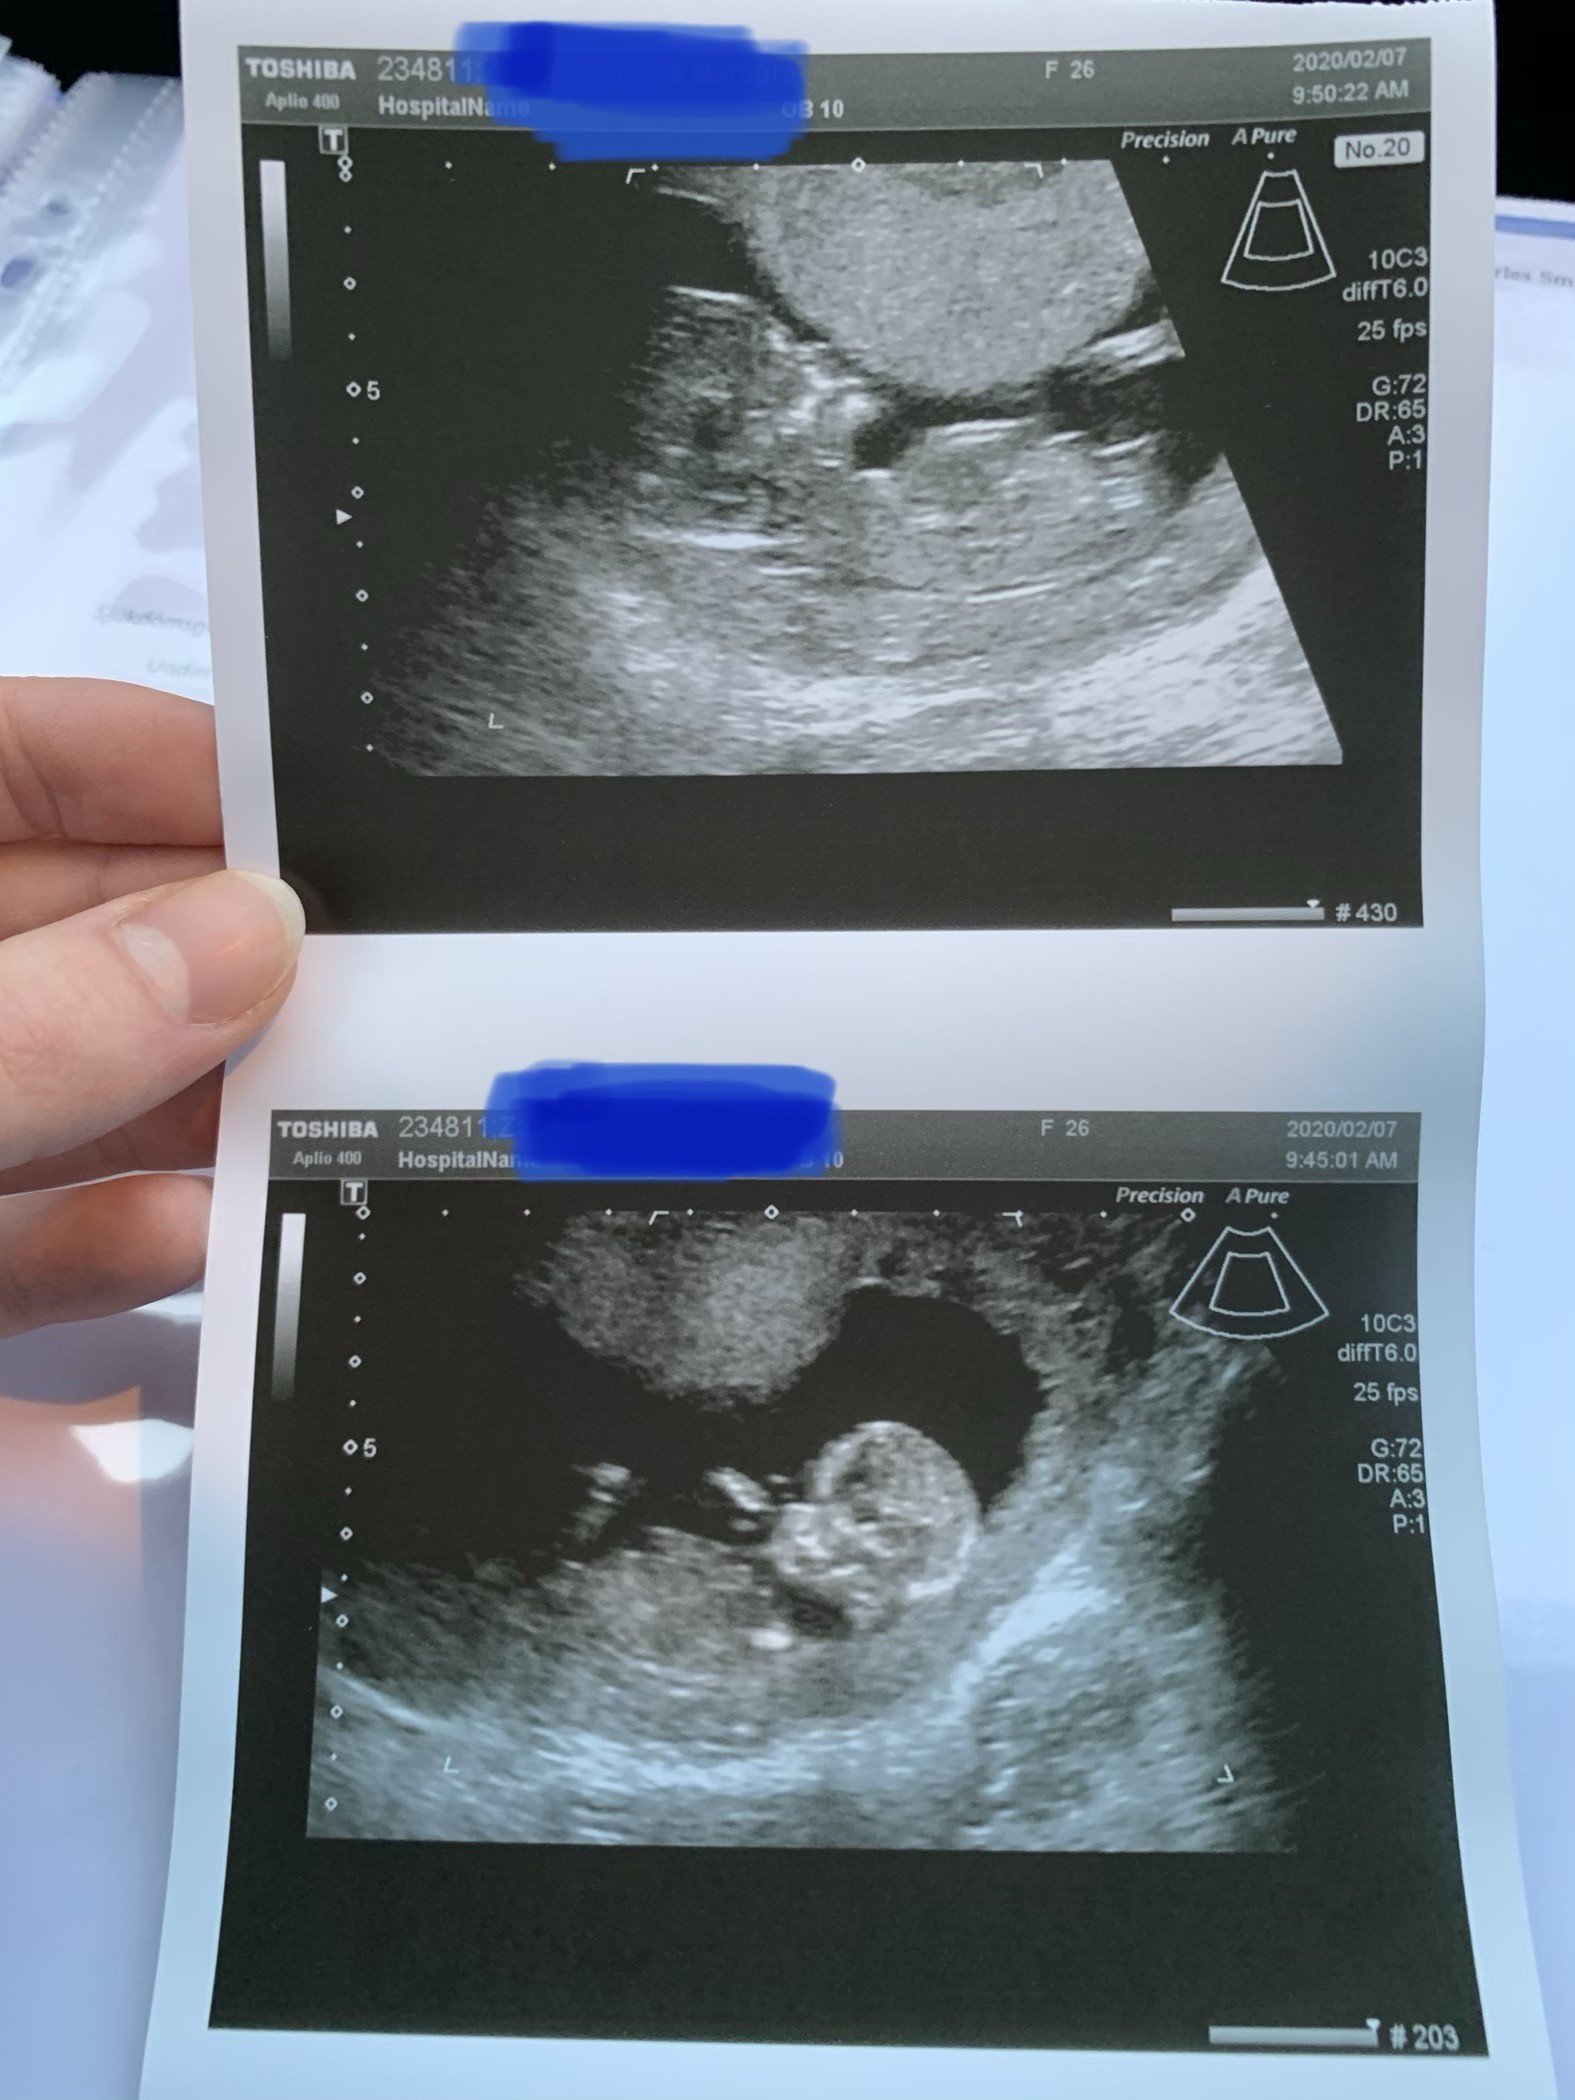

Przedstawiam Wam moją „france” nie pokazało dzieciątko co ma „w spodniach”

Ale za to były tańce i swawole 😂😂 a pózniej głęboko sen i za nic w świecie nie chciało się obudzić 🤦🏼‍♀️ Uparte po ojcu 😎

Najważniejsze, że wszystko wyglada dobrze ❤️